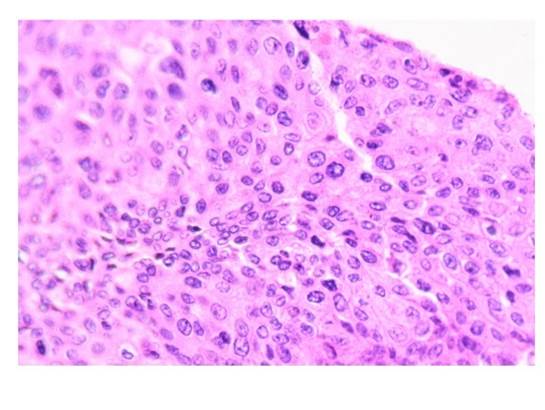

El reporte histopatológico del lado derecho revela carcinoma urotelial papilar invasor de alto grado pT3N0M0 dependiente de pelvis renal que se extiende únicamente hasta el tercio proximal del uréter ipsilateral, el cual se encuentra confinado al tejido renal con invasión focal al parénquima medular, sin invadir el seno renal y sin identificar afección a la capsula renal; invasión renovascular presente (Imagen 5 y 6).

La imagen demuestra carcinoma urotelial de tipo papilar.

Imagen 6 Corte histológico de pieza quirúrgica derecha